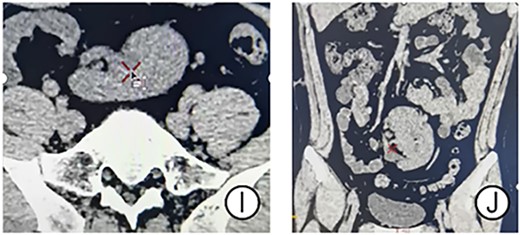

After communicating with the patient, we performed a RALP. The surgery used a transabdominal approach, and an ectopic kidney was seen on the right side of the lower abdomen with a markedly dilated hydronephrosis. A fibrous strip was removed from the pelvic ureteral junction, and a 5 Fr double ‘J’ catheter was put directly into the ureter (Fig. 2E–G). The operation took 175 min. Postoperative pathological findings are irregular proliferation of surrounding fibrous and smooth muscle tissue (Fig. 2H). The patient’s pain disappeared after surgery. No complications occurred such as urinary leakage or urinary tract infection during the perioperative period. The patient was discharged from hospital 3 days after the surgery. Double ‘J’ catheter was removed 6 weeks after surgery. The blood of urea nitrogen was 4.30 mmol/L, the serum creatinine was 92 μmol/L and the GFR was 101.350 ml/min 3 months after the surgery. CT showed significant reduction in hydronephrosis (Fig. 3I and J).

CT results of the patient’s postoperative follow-up. (I and J) CT showed significant disappearance of the effusion.